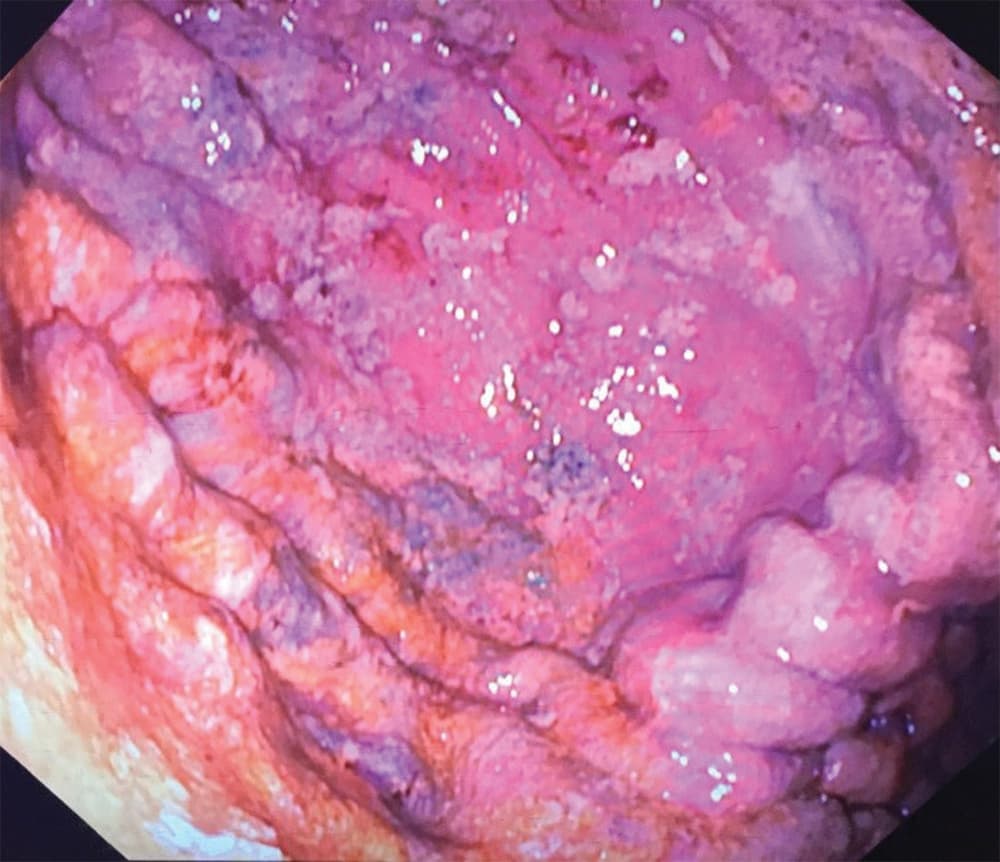

Regastroskopi foretaget 18-19 timer efter indtag af jerntabletter. Der ses punktvise slimhindenekroser og rester af jerntabletter i ventriklen.

En kvinde i 20’erne blev indlagt tre timer efter i suicidalt øjemed at have indtaget 300 stk. jern C-tabletter (indeholder 330 mg ferrofumarat = 100 mg elementært jern), hvilket svarer til en jerndosis på 400 mg/kg. Ved indlæggelsen var patienten uden somatiske symptomer og P-jernniveauet blev målt til 82 µmol/l. En oversigt over abdomen (OOA) viste store mængder jerntabletter i ventriklen (Figur 1), og der blev påbegyndt behandling med antidoten deferoxaminmesilat samt udført gastroskopi i forsøg på dekontaminering. Man fandt en ødematøs slimhinde og et stort bezoar bestående af en tyk masse af føderester og delvist opløste jerntabletter, hvoraf hovedparten blev udhentet. P-jernniveauet faldt herefter til 49 µmol/l. En fornyet OOA viste resterende jerntabletter i ventriklen og spredt i tyndtarmen, hvorfor der blev udført regastroskopi med evakuering af restbezoaret. Behandling med macrogollaksantia blev initieret (en såkaldt »tarmskylning«) for at fremskynde tarmtømningen pga. jerntabletterne i tyndtarmen. Pga. betydelig perforationsrisiko blev patienten overflyttet til klinisk observation på en intensivafdeling på et højtspecialiseret hospital. Her fortsatte man med tarmskylning i to døgn, hvorefter patienten blev udskrevet til en psykiatrisk afdeling efter fire døgns indlæggelse. Efterforløbet var uden tegn til komplikationer eller organskader.